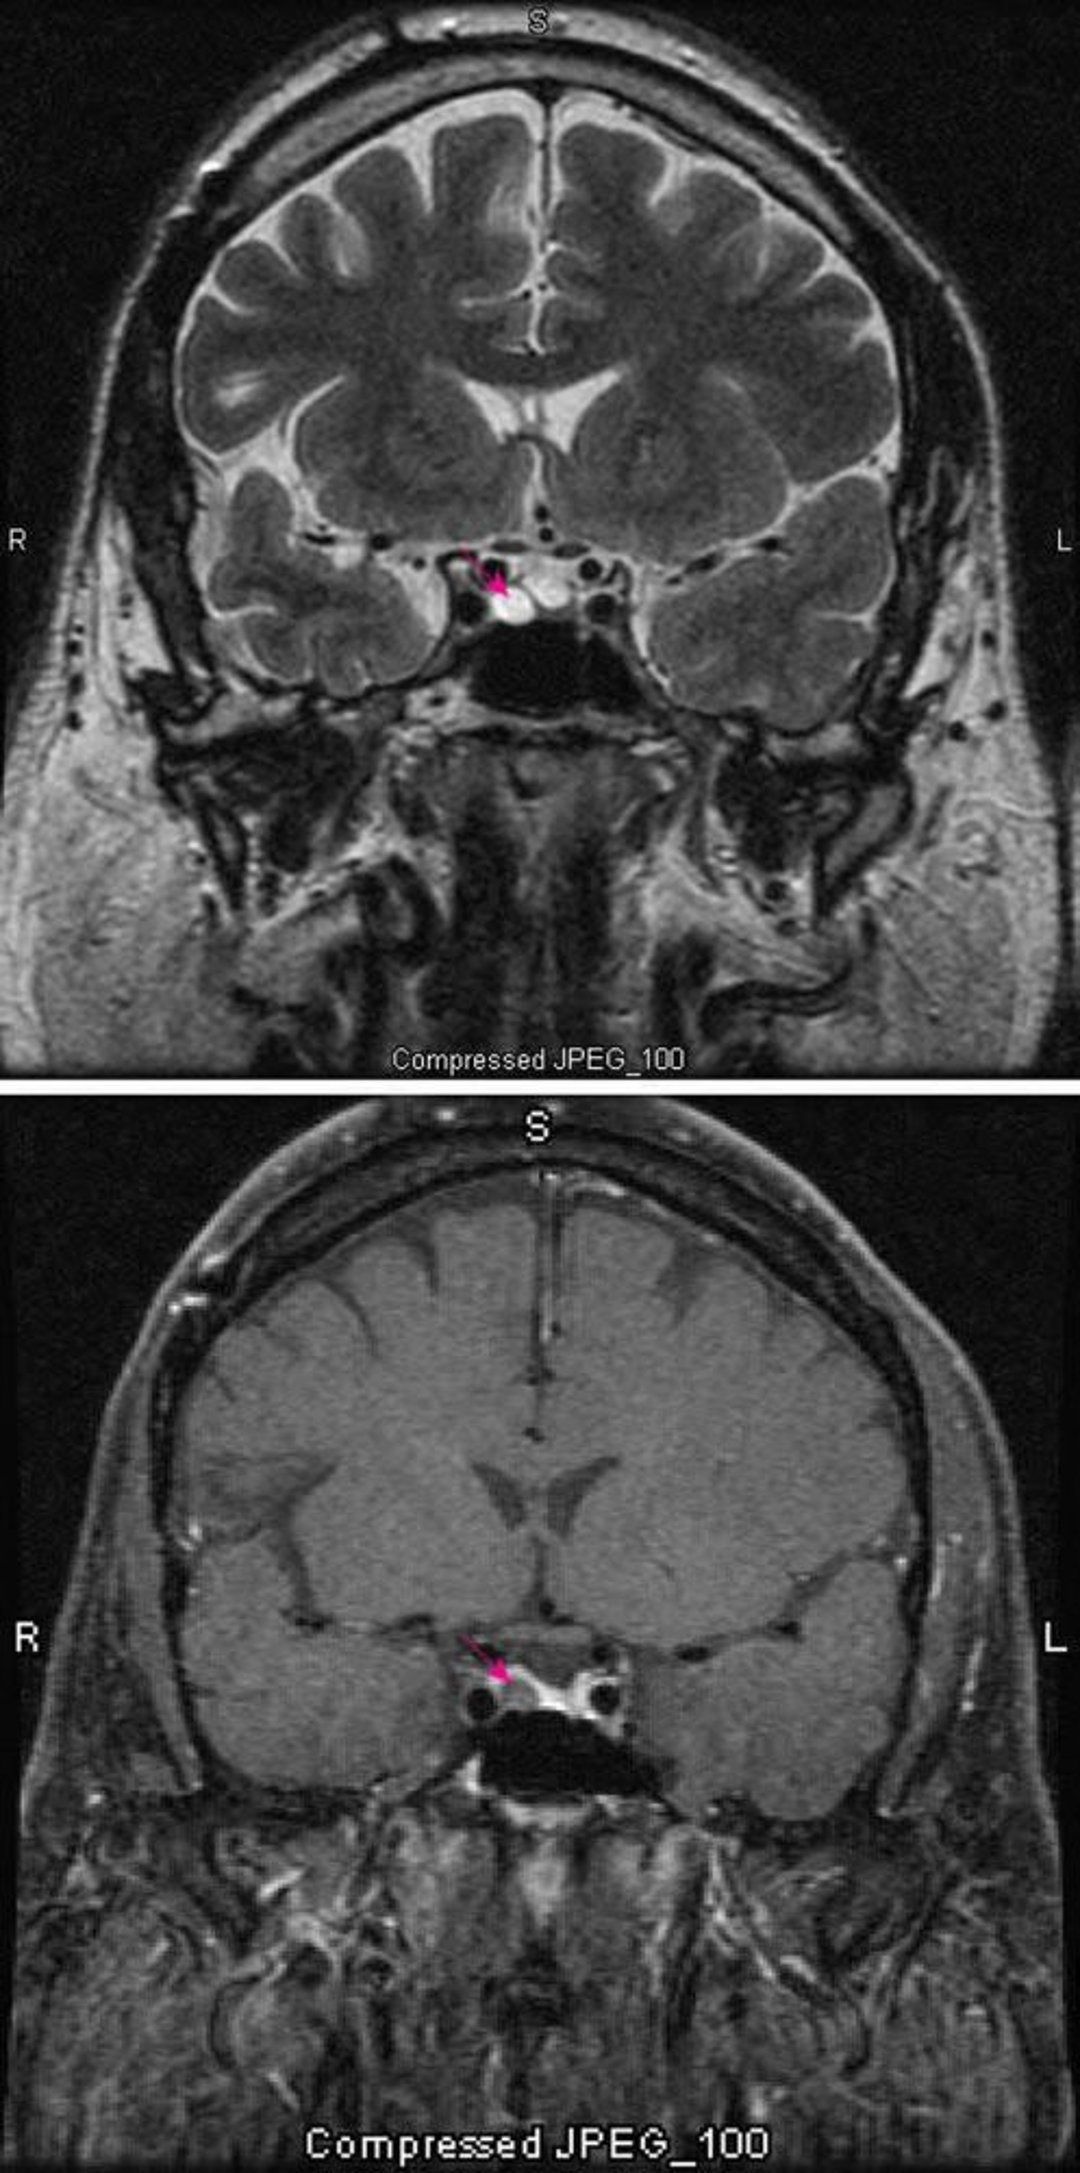

Microadénome hypophysaire

L'IRM pondérée en T2 (en haut) montre un microadénome hypophysaire (flèche rouge). Le produit de contraste (en bas) améliore normalement la visualisation de l'hypophyse (flèche rouge). L'adénome semble plus clair.

Images courtesy of William R. Shapiro, MD.